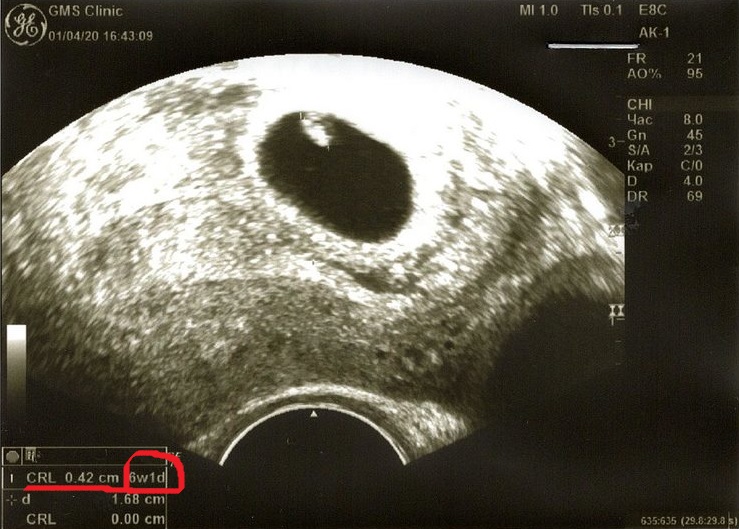

В аппарате узи установлена программа, которая сама определяет акушерский срок в зависимости от размера эмбриона и пр. признаков, собственно по такой же схеме рассчитывается и предполагаемый вес плода. Если посмотрите свои снимки узи, можете увидеть, как там акушерский срок отражен. А в заключении вам уже врач, что захочет то и напишет:)))